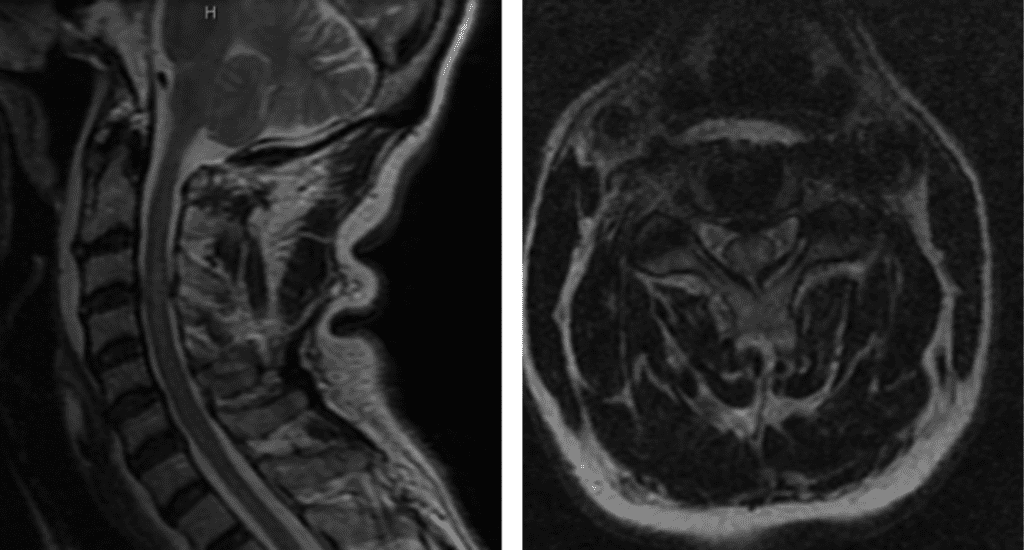

Figure 1. T2 MRI sagittal and axial showing C3/C4 disc herniation with compression of the spinal cord; spinal cord edema at the C3/C4 level.

This patient was suffering from compression of the cervical spinal cord. The fall caused an acute herniation of the cervical disc, which caused pressure on the spinal cord.